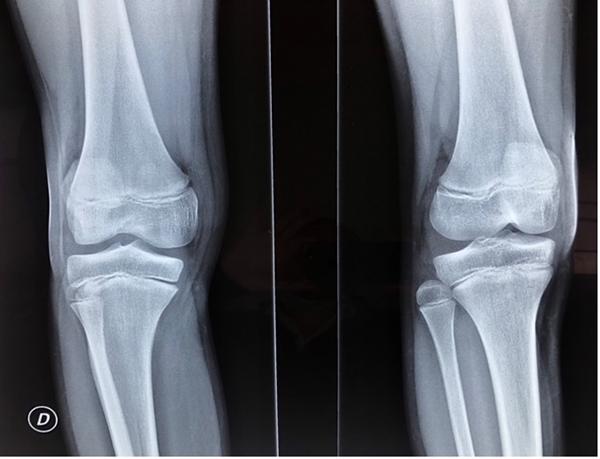

El paciente refería nunca haber requerido una maniobra de reducción para la inestabilidad tibioperonea proximal, simplemente con el cese de la actividad aliviaba el dolor y “desaparecía” el resalto óseo que percibía. Se realizó radiografía de rodilla frente y perfil en la que se pudo apreciar la pérdida parcial de las relaciones articulares entre la tibia y el peroné proximal (fig. 1). Se completó el estudio imagenológico con una resonancia magnética (RM) donde se observó rotura intrasustancia del ligamento tibioperoneo proximal (LTPP) (fig. 2).

Figura 1: Radiografía oblicua interna y externa de rodilla derecha. Se puede observar cómo el peroné se encuentra lateralizado y posterior con respecto a la tibia, sugestivo de lesión de la articulación tibioperonea proximal.

En la actualidad, con tres años de seguimiento, el paciente no presenta dolor, no refiere inestabilidad y tiene un rango de movimiento completo en su rodilla. Las maniobras de traslación anteroposteriores de peroné son negativas y no volvió a notar resaltos óseos durante la práctica deportiva. Se realizaron radiografías en estrés que no muestran diferencia con la rodilla contralateral y se le realizó una RM de control que evidencia una correcta reducción de la articulación TPR y un injerto completamente incorporado (fig. 5). Actualmente realiza deportes de alta competencia sin limitaciones.